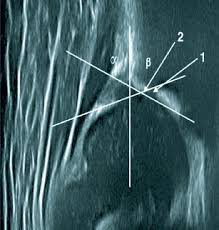

Η εξέταση πραγματοποιείται με τη μέθοδο Graf, η οποία αποτελεί διεθνές πρότυπο.

- Εμπειρία στη μέθοδο Graf (ο κ.Νικόλαος Καλύβας είχε την τύχη και την τιμή να εκπαιδευτεί στον Υπερηχογραφικό έλεγχο των νεογνικών ισχίων από τον ίδιο τον Reinhard Graf )